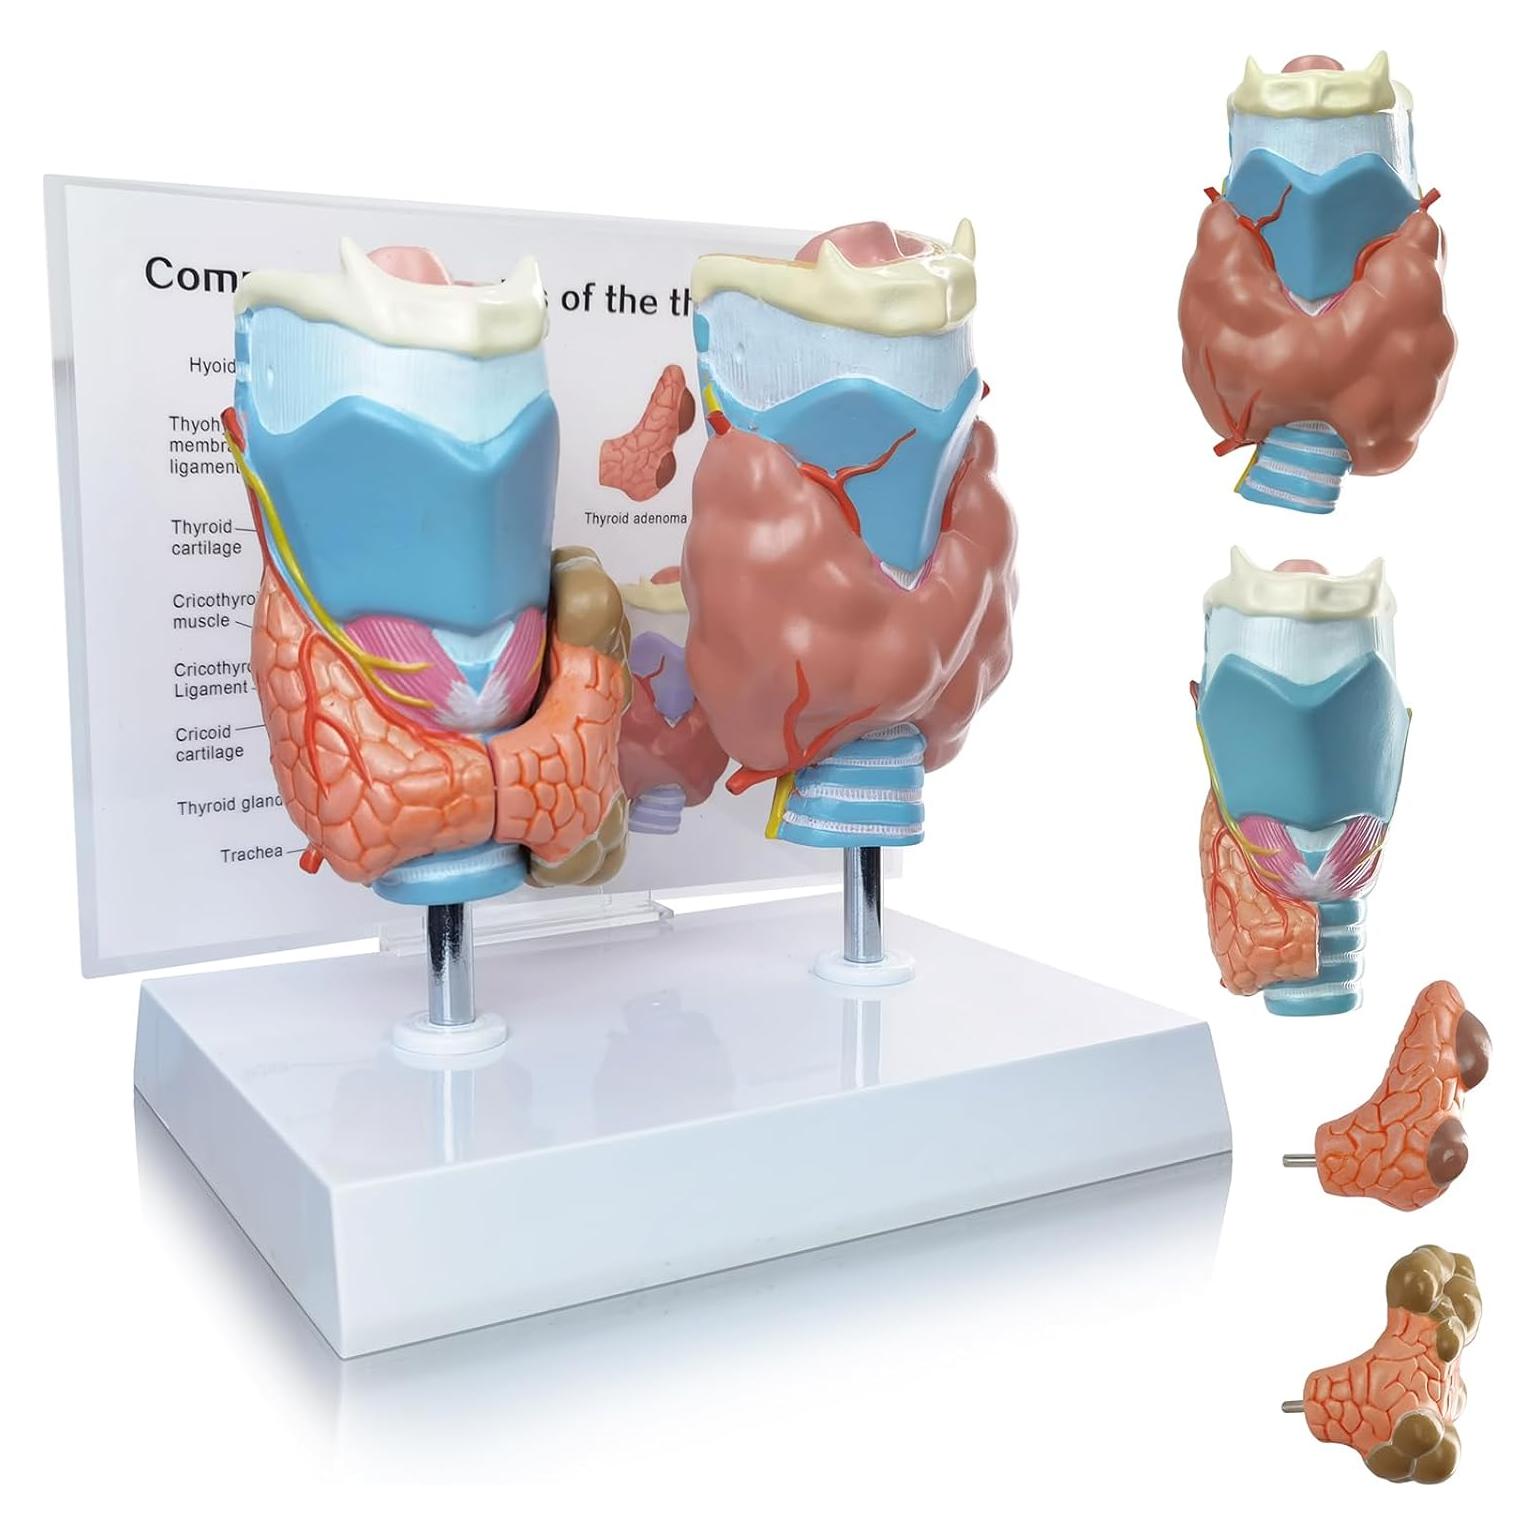

Modelos Anatómicos de Órganos marca Evotech (20 productos)

Modelos Anatómicos 3D EVOTECH SCIENTIFIC - Cuerpo, Corazón y Esqueleto